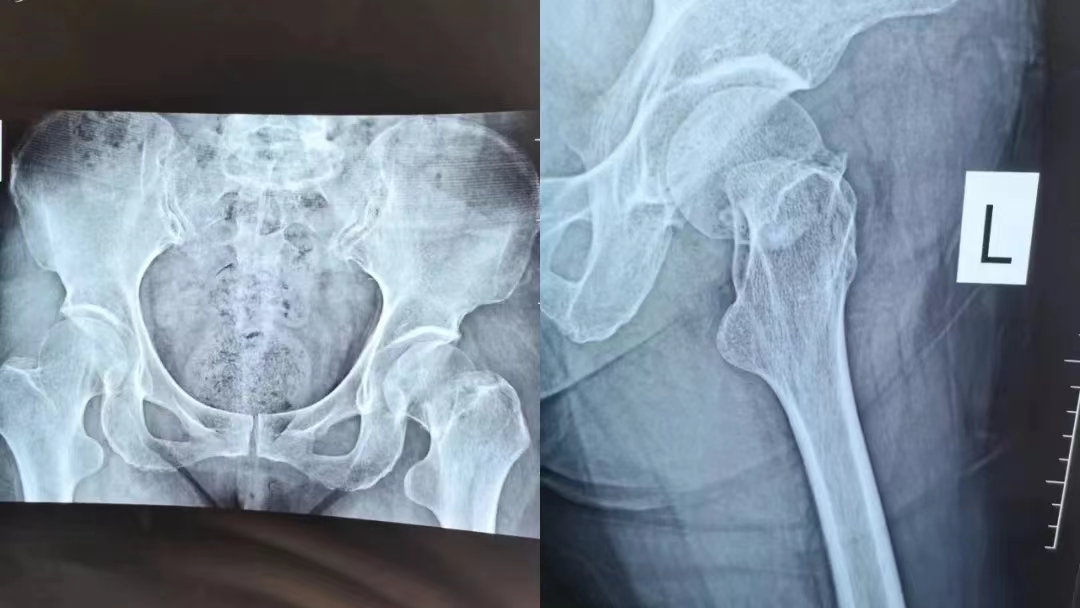

患者应某,今年79岁,在家不小心摔伤。受伤以来,应奶奶只感觉左髋部疼痛、肿胀、活动受限,并无其他症状发生,家人也没有太过在意。直到10天后,应奶奶髋部疼痛和肿胀情况不见好转,甚至疼痛加剧,家属于10月27日送至我院外科就诊,外科副主任程广东医师亲自接诊了老人,在仔细询问了应奶奶的病史后,经CT及相关辅助检查诊断为“左股骨颈骨折”。

术前X线片